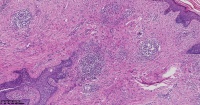

纤维瘤?

性别

女

年龄

22岁

右侧面部丘疹10年

面部包块

纤维组织瘤样增生,伴慢性炎细胞浸润。

形态有点像疤痕。

考虑孤立性纤维性肿瘤,建议IHC:CD31,CD34标记明确。